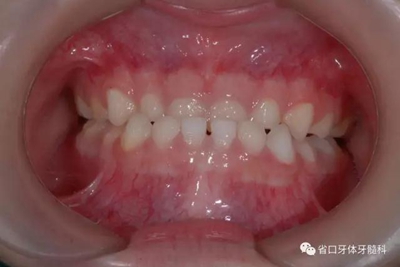

圖4 正面牙相(2015年1月)

5.jpg

圖5 左側45度牙相